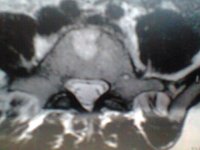

ich versuch es einfach mal...also ich hab seit ca 2 Jahren einen Bsv L4/L5 bislang ohne OP...

ich war 4 Wochen in reha danach habe ich die Wiedereingliederung gemacht und arbeite seitdem wieder in Vollzeit ( seit September 2011 ) jetzt seit 1 Monat habe ich wieder starke schmerzen und dazu gekommen ist mein Steißbein,kann kaum sitzen und beim aufstehen tut es höllisch weh

arbeiten geh ich zur zeit nur 5-7 Std danach geht nicht mehr.....nehme seit ca 7 Monaten Targin 20mg/10 mg 3 mal am Tag...so wirklich lange helfen die leider auch nicht mehr...Heute war ich beim MRT könnte jemand von euch mir die ein bissel beschreiben????